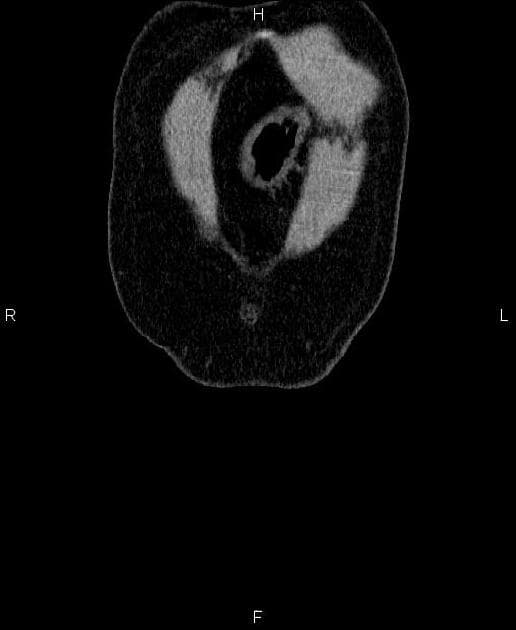

- Một khối nang khu trú một phần lồi ra ngoài (exophytic) kích thước 48 mm, thành dày ngấm thuốc (enhancement) và có các vách ngăn cùng các nốt ngấm thuốc lệch tâm (eccentric enhancing nodules) được ghi nhận ở phần giữa của thận phải.

Khối nang thận - phân loại Bosniak IV (Renal cystic mass - Bosniak class IV)

- "Các khối nang thận phân loại Bosniak IV có nguy cơ ác tính từ 70-90% và thường là ung thư biểu mô tế bào thận dạng nang."

- "Các đặc điểm hình ảnh chính bao gồm thành dày ngấm thuốc, vách ngăn ngấm thuốc và các nốt ngấm thuốc lệch tâm."